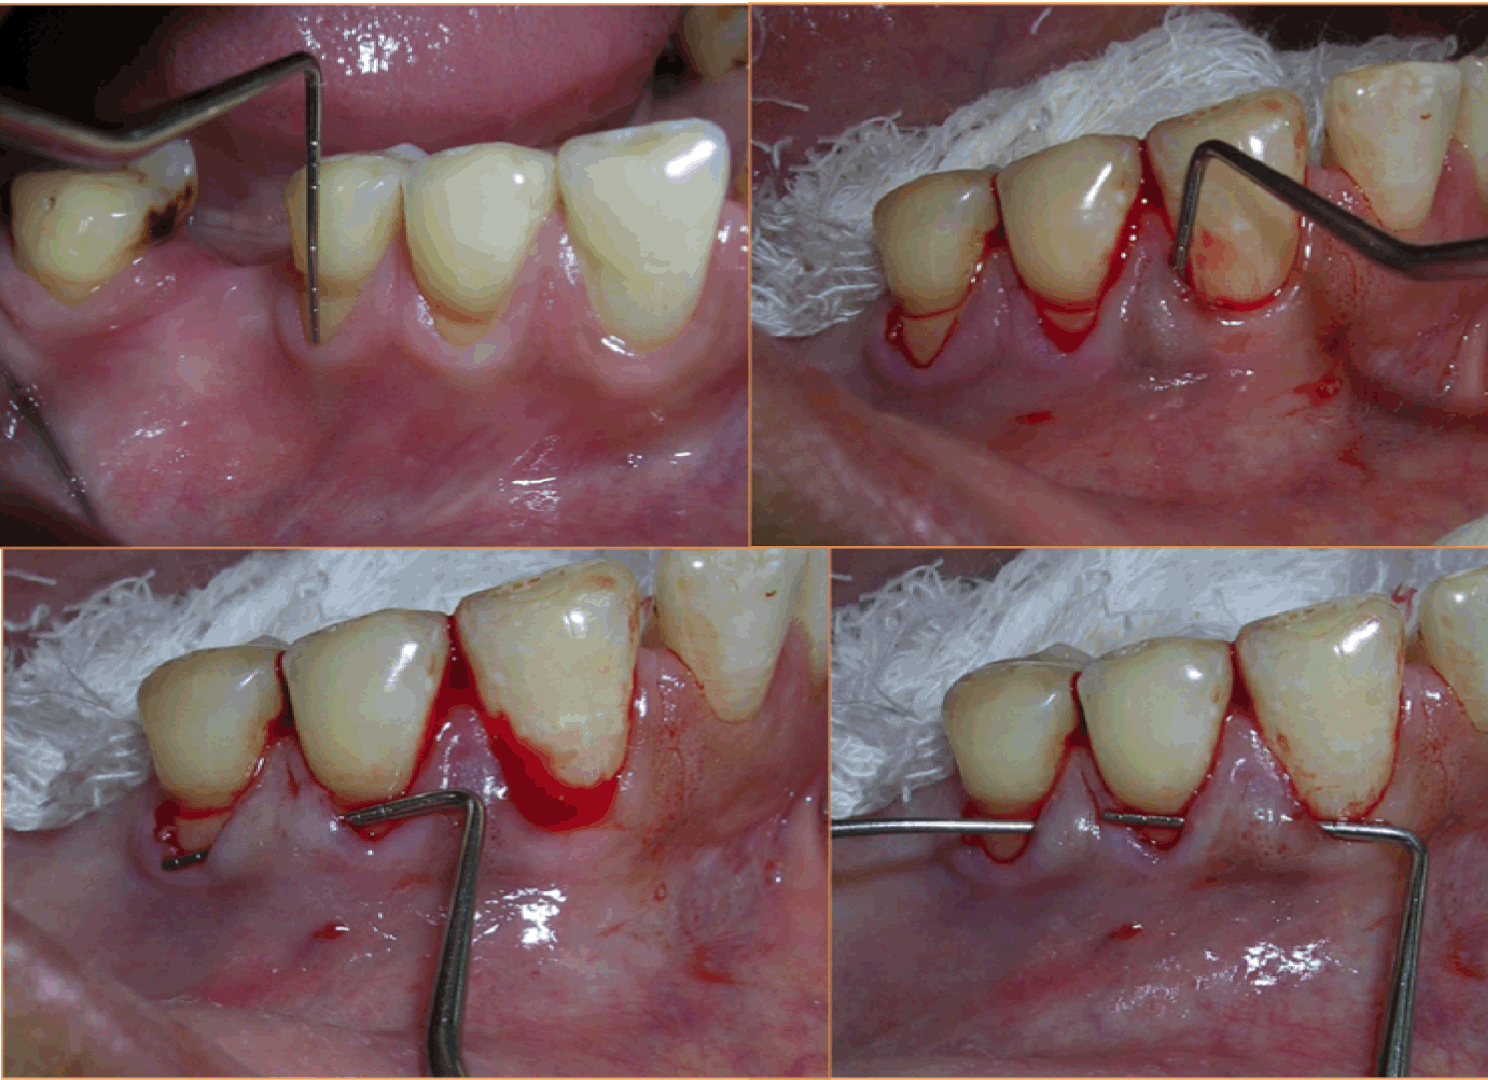

Case 1: A 36-year-old female reported with the chief complaint of sensitivity in lower right posterior teeth. On examination there was Millers Class III recession in relation to 44 and 45 (Figure 1). The width of attached gingiva was found to be inadequate since the tension test was positive. After phase I therapy, a pouch and tunnel technique utilizing a connective tissue graft was planned for root coverage. A sulcular incision was made through each recession area and the tissues gradually undermined including the base of the interdental papilla without the tip and the undermining extended up to the mucogingival junction so as to relax the flap sufficiently to allow placement of the connective tissue graft. Thus gradually a pouch and tunnel was prepared connecting the recipient sites for placement of the graft (Figure 2). The connective tissue graft was harvested from the palate using Liu's Class 1a incision (Figure 3). This graft was then placed using a technique described by Zabaluigi et al. where two resorbable sutures of different colors were placed, one on either side of the graft. Using these sutures, the graft was gradually manipulated into the pouch and through the tunnel to cover the adjacent recipient sites. Once the graft was completely inside the tunnel, it was positioned coronal to the cemento-enamel junction. The ends were sutured with a simple square knot (Figure 4). A periodontal pack was placed both at the recipient site as well as the donor site using an acrylic stent for the palatal placement.

Figure 2: Pouch and tunnel preparation (Case 1).

Figure 4: The graft placed into the tunnel and sutured.